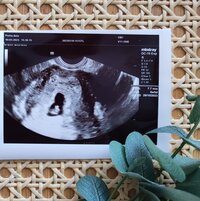

Laitetaan tännekkin. VU käyty ja pieni löytyi oikeasta paikasta sykkeen kera. 🥰 Koko vastasi viikon vähemmän, mitä alunperin laskettiin mutta johtunee koronan sekoittamista kierroista. Eli tänään 6+3 🥰